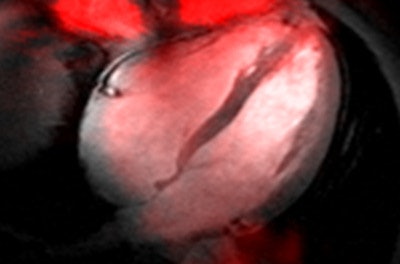

Above: Sodium (Na-23) MR image (red) of a four-chamber view of the human heart superimposed to a 2D CINE image (gray). The Na-23 image of the heart was acquired at 7 tesla using a density-adapted short echo-time 3D radial technique. Below: Fluorine (F-19) MR image (red) of an axial view through the human knee superimposed to an anatomical image (gray). The F-19 image was acquired at 7 tesla following topical application of an ointment containing flufenamic acid -- an F-19-containing nonsteroidal anti-inflammatory drug (NSAID). A spatial resolution of (1.5 x 1.5 x 5.0) mm3 was accomplished.Moreover, the benefits of 7-tesla innovations are already being seen at 3 tesla, where the suboptimal copy and paste approach to protocol migration from 1.5 tesla is being supplanted by the sort of application-targeted redesign that is essential at UHF. Recognizing the pace and momentum of UHF-MR, the MR vendors committed that there is no U-turn on the tesla road. In fact, they are now driving with full throttle to set up the next generation of whole-body 7-tesla systems with CE certification or U.S. Food and Drug Administration (FDA) approval eventually looming on the horizon.

One exciting development that is in the spotlight of current (pre)clinical research is that cutting-edge MR centers are exploiting UHF-MR not only for H-1 MRI but also for documenting the value of 7-tesla MRI for imaging x-nuclei such as carbon (C-13), oxygen (O-17), fluorine (F-19), sodium (Na-23), phosphorous (P-31), chlorine (Cl-35), and potassium (K-39). UHF-MR holds the promise to facilitate sodium imaging of the heart (see figure) with a spatial resolution commonly used for H-1 MR in today's clinical practice at lower fields.1